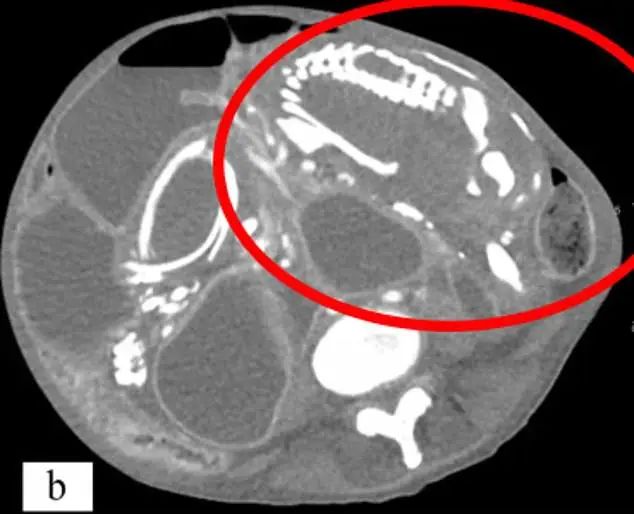

「石胎」導致小腸梗阻、常年消化不良

根據 CT 掃描的發現,她的腹中有一個長15至20cm的石胎,能清晰看到胎兒的骨架。因為石胎體積較大,導致她的小腸梗阻、大靜脈受壓迫、盆骨壓迫、高血壓和感染了幽默螺桿菌、常年消化不良、腹痛。由於鈣化的石胎壓迫大小腸,她一吃多就吐,嚴重的時候吐膽汁,所以不敢多吃,導致營養不良,體質很弱,而她也因為害怕「詛咒」而拒絕了所有口服藥物。